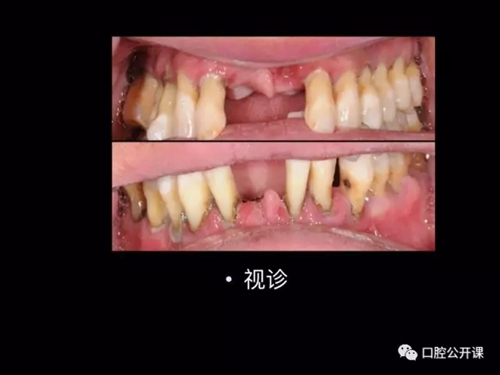

一例廣泛型侵襲性牙周炎5年臨床追蹤下

楊淑銀醫(yī)師用他的一例侵襲性牙周炎五年臨床病例追蹤來(lái)縮影一個(gè)青年牙周醫(yī)師的成長(zhǎng)之路,帶我們一起探索看似平凡枯燥的牙周基礎(chǔ)治療到底有怎樣的重要性?